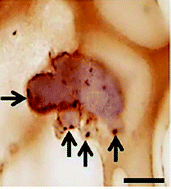

Intestinal stem cells hold great potential in tissue regeneration of the intestine, however, there are key limitations in their culture in vitro. We previously reported a novel synthetic non-biodegradable hydrogel as a 3D culture model for intestinal epithelium using Caco2 and HT29-MTX cells. Here, we investigated the potential of this system as a 3D scaffold for crypts and single intestinal stem cells to support long-term culture and differentiation. Intestinal crypts were extracted from murine small intestines and Lgr5+ stem cells isolated by magnetic activated cell sorting. Crypts and stem cells were suspended within Matrigel or L-pNIPAM for 14 days or suspended within Matrigel for 7 days then released, dissociated, and suspended within, or on L-pNIPAM hydrogel for 28 days. Cellular behaviour and phenotype were determined by histology and immunohistochemistry for stem cell and differentiation markers: Lgr5, E-cadherin MUC2 chromograninA and lysozymes. Isolated crypts and Lgr5+ intestinal stem cells formed enteroids with a central lumen surrounded by multiple crypt-like buds when cultured in Matrigel. In contrast, when crypts and stem cells were directly suspended within, or layered on L-pNIPAM hydrogel under dynamic culture conditions they formed spherical balls of cells, with no central lumen. When enteroids were initially formed in Matrigel from crypts or single Lgr5+ intestinal stem cells and dissociated into small fragments or single cells and transferred to L-pNIPAM hydrogel they formed new larger enteroids with numerous crypt-like buds. These crypt-like buds showed the presence of mucin-producing cells, which resembled goblet cells, scattered throughout their structures. Immunohistochemistry staining also showed the expression of Lgr5 and differentiation markers of all the main intestinal cell types including: enterocytes, goblet cells, enteroendocrine and Paneth cells. This demonstrated that L-pNIPAM hydrogel supported long-term culture of crypts and Lgr5+ stem cells and promoted intestinal cell differentiation.